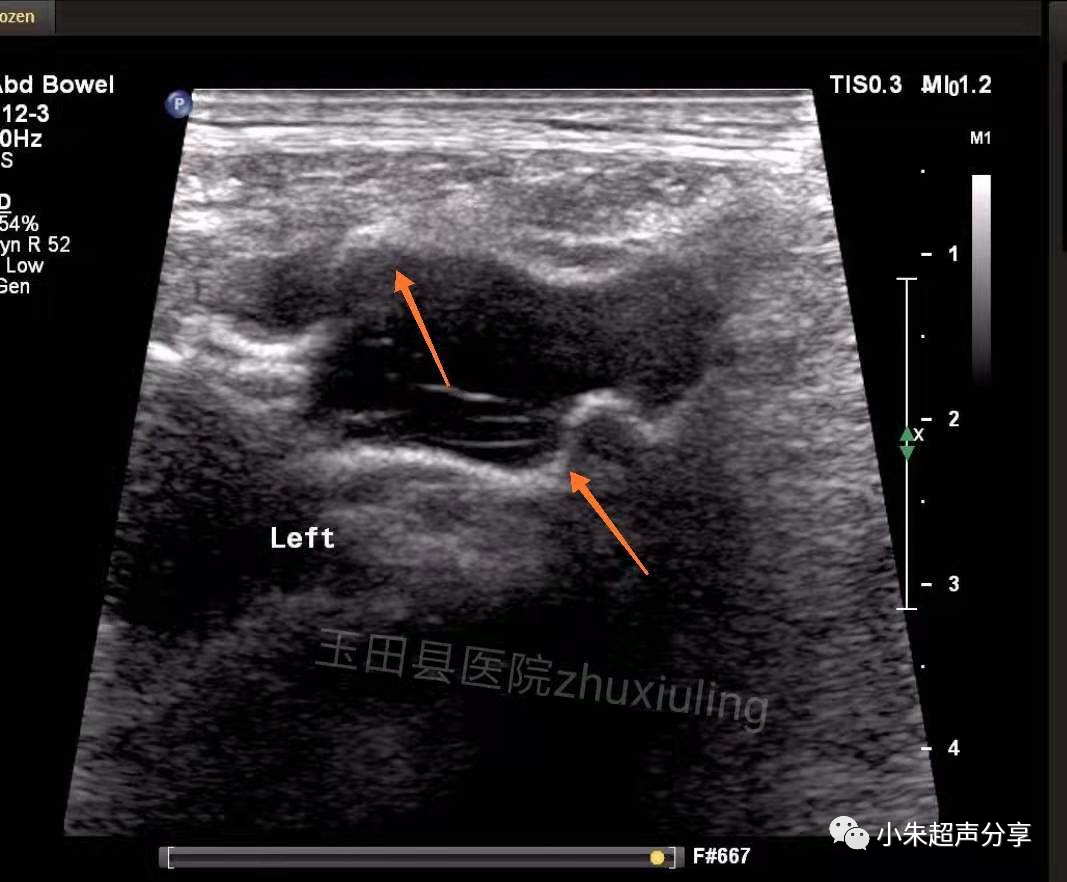

Case2:男,双侧腹股沟疝术后1月,双侧腹股沟区及阴囊疼痛,左侧为著。

血清肿常表现为边界不清、形态不规则、透声差的无回声区,持续时间长者积液内可见多发分隔,无血流信号。在其内部或周边常可见到补片结构,病程长者,补片可卷曲变形呈波浪状(如Case2)。发现时应及时与手术医生沟通,必要时需多次穿刺抽吸,并需定期复查。Case1患者经抽液2次后好转出院(第1次抽出50ml淡红色液体,隔日抽出45ml淡黄色液体)。Case2患者经门诊保守治疗后痊愈。

该2例患者积液发生的部位亦有所不同,Case1患者积液位于右下腹腹腔内并与腹股沟区相通(考虑积液位置为原疝囊内),可能残留狭小缝隙,但未见腹腔内容物疝出;Case2患者积液局限于腹股沟区腹壁软组织内,未见与腹腔相通。